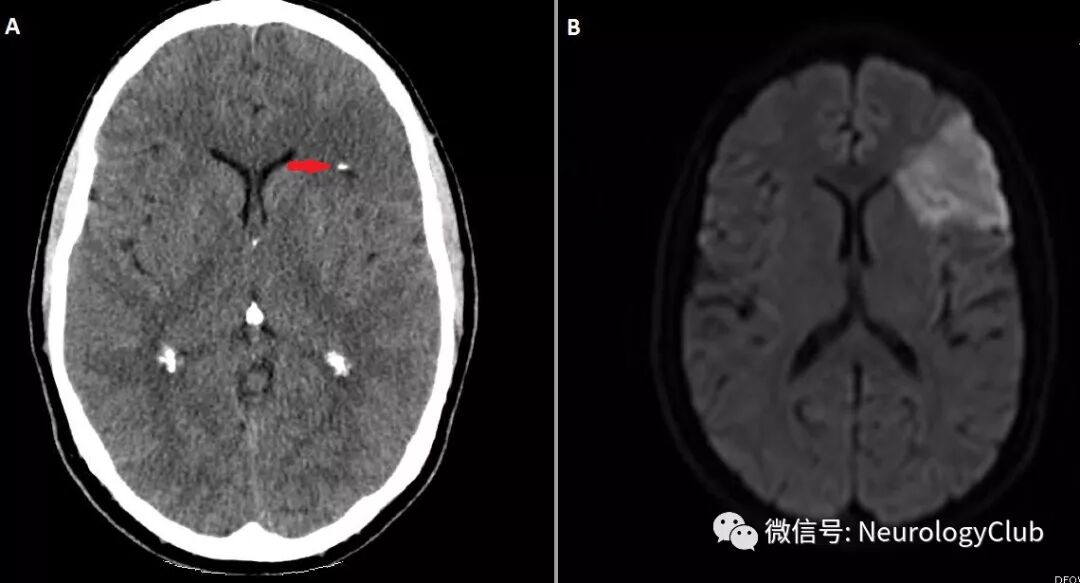

(图2:A:临床症状恶化后复查头颅CT提示新发钙化病灶,远处灰白质分界不清;B:DWI证实为缺血性卒中)

患者表现为凸面蛛网膜下腔出血伴出血区和动脉内小钙化灶(图1)。进一步查体可闻及新发较响的收缩期杂音。给予经验性抗感染性心内膜炎治疗。4小时后患者症状恶化,出现表达性失语。复查影像学可见新发钙化病灶和缺血性卒中(图2)。超声心动图提示二尖瓣赘生物伴钙化(图3)。血培养可见副血链球菌生长。